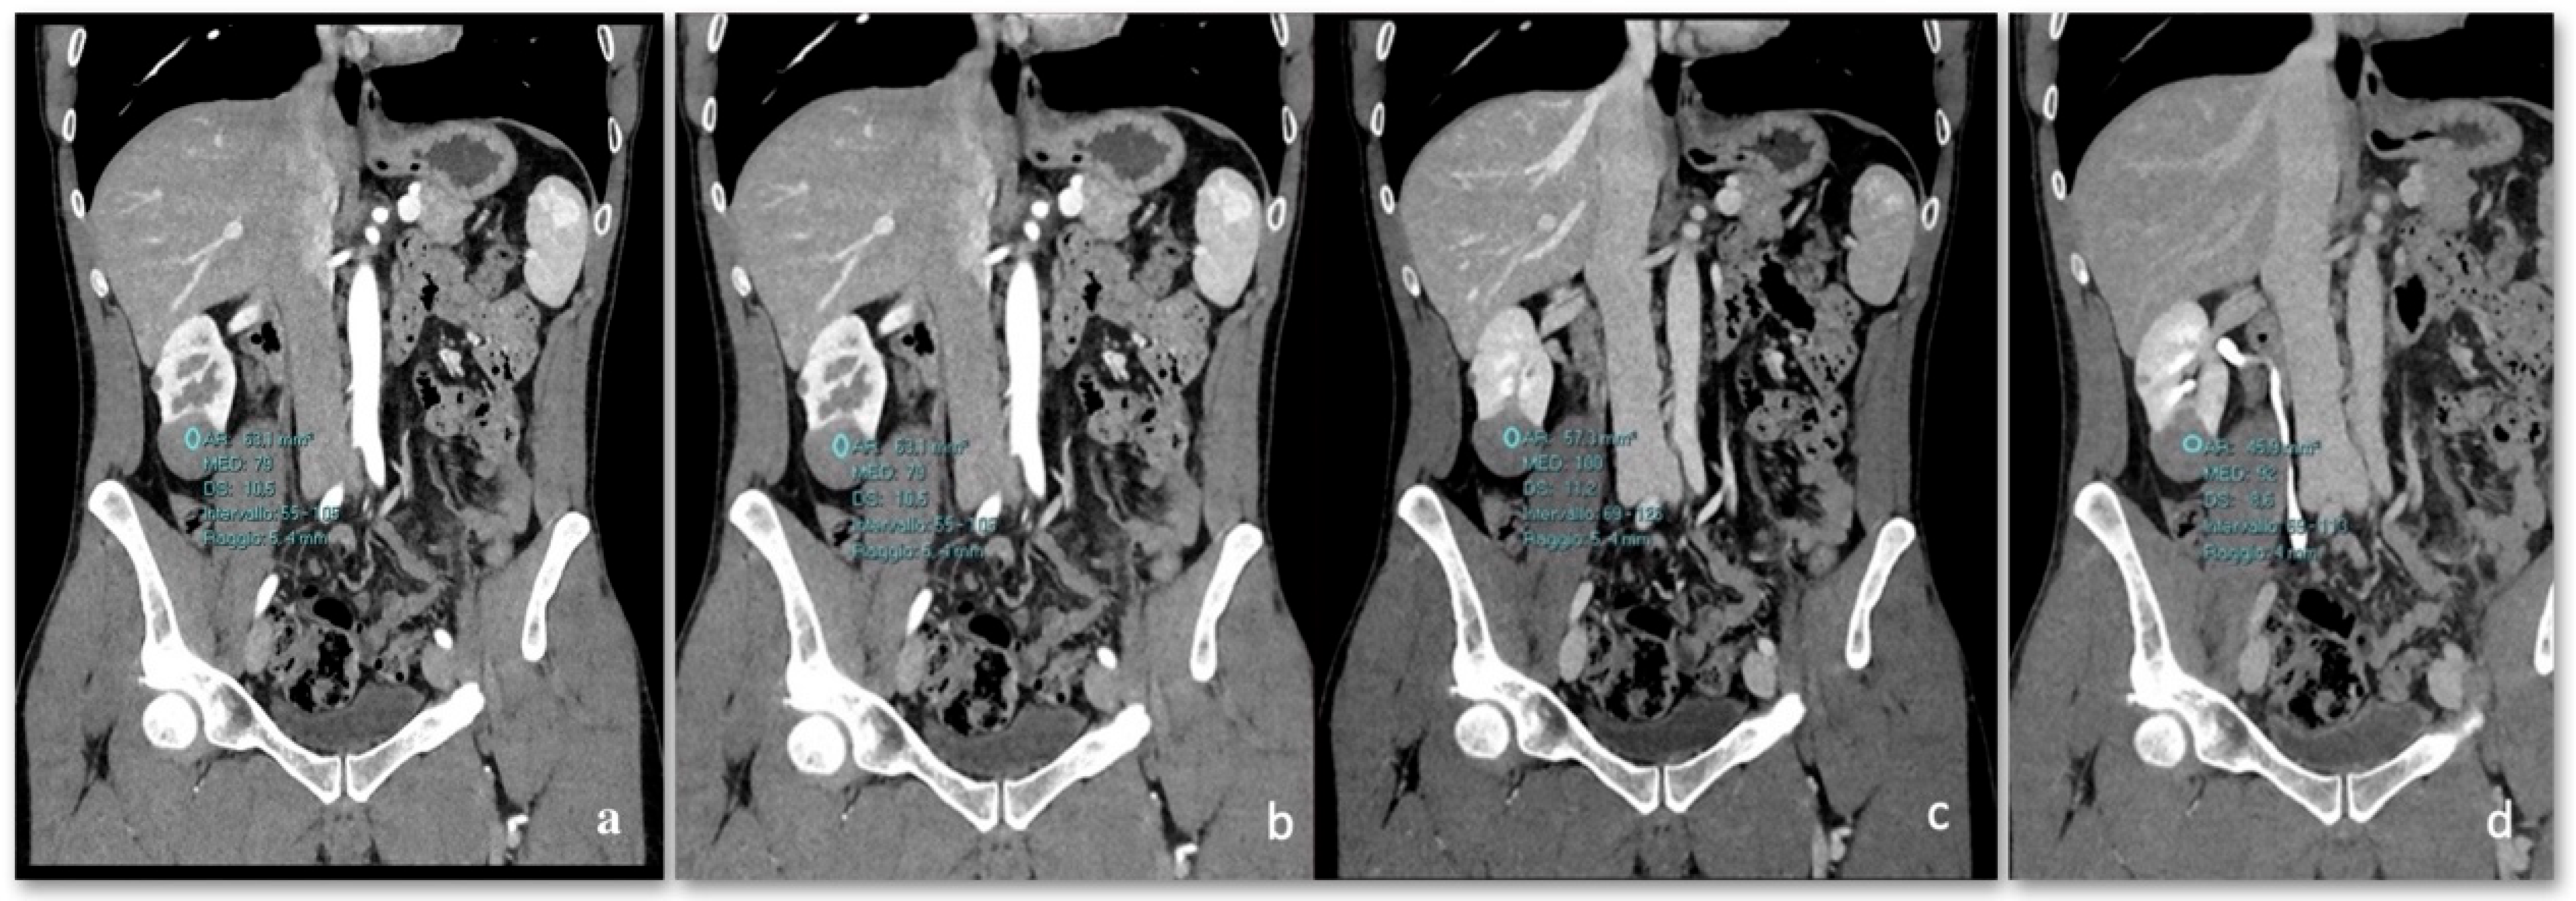

3.3. CT

Density and Contrast Enhancement

- Pre-enhanced phase: 30.3 ± 6.5 HU.

- Arterial phase: 47.2 ± 12.4 HU.

- Venous phase: 64.6 ± 17.3 HU.

- Delayed phase: 61.8 ± 14.5 HU.